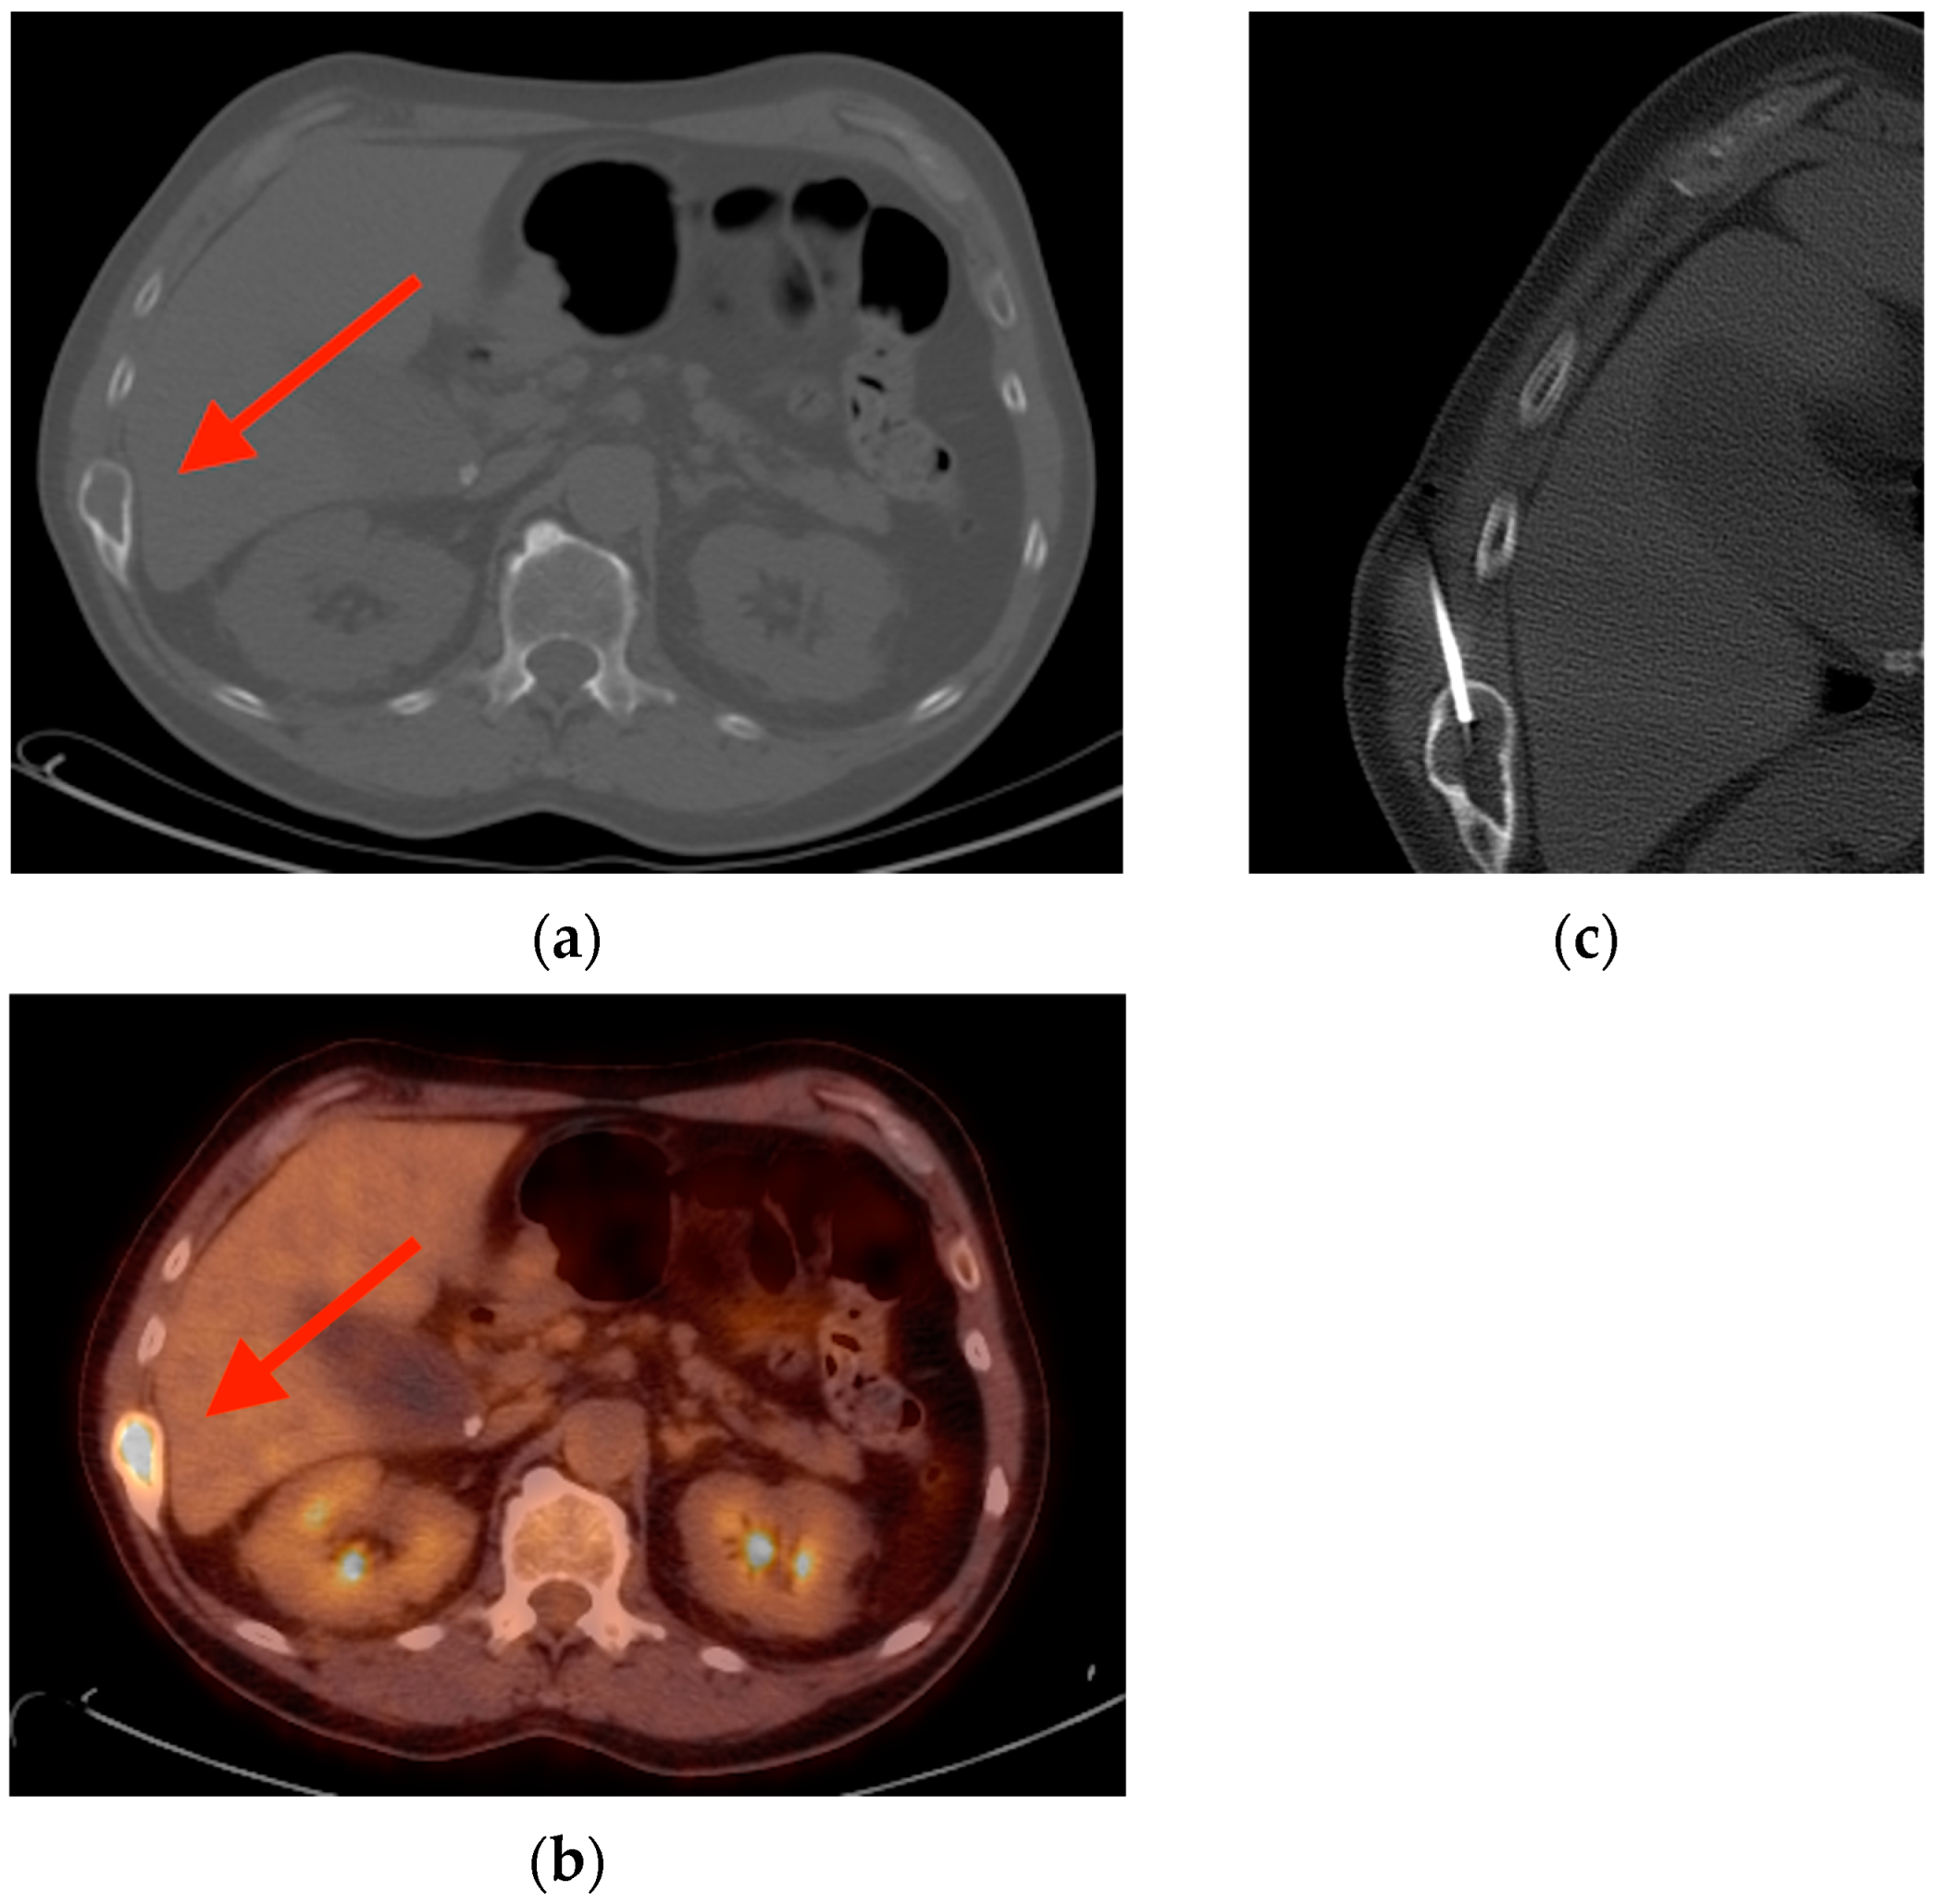

2.2. Fibrous Dysplasia

- Su, M.G.; Tian, R.; Fan, Q.P.; Tian, Y.; Li, F.L.; Li, L.; Kuang, A.; Miller, J.H. Recognition of fibrous dysplasia of bone mimicking skeletal metastasis on 18F-FDG PET/CT imaging. Skelet. Radiol. 2011, 40, 295–302. [Google Scholar] [CrossRef]

- Ribeiro, A.M.B.; Lima, E.N.P.; Rocha, M.M. Fibrous dysplasia as a possible false-positive finding in 68Ga-labeled prostate-specific membrane antigen positron emission tomography/computed tomography study in the follow-up of prostate cancer. World J. Nucl. Med. 2019, 18, 409–412. [Google Scholar] [CrossRef]

- Kushchayeva, Y.S.; Kushchayev, S.V.; Glushko, T.Y.; Tella, S.H.; Teytelboym, O.M.; Collins, M.T.; Boyce, A.M. Fibrous dysplasia for radiologists: Beyond ground glass bone matrix. Insights Imaging 2018, 9, 1035–1056. [Google Scholar] [CrossRef]